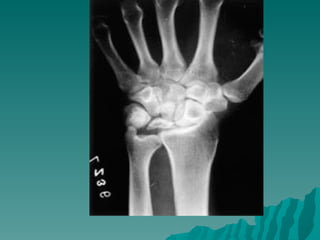

Keinböck hastalığı  Genellikle yetişkinlerde ve unilateral  El bileğinde ağrı ve hassasiyet r  Travmalar ve tekrarlayan mikrotravmalar Rober Kienböck (1871 -1953) suçlanır.  X-Ray: lunat kemikte yaygın opasite kemikte yassılaşma, fregmantasyon